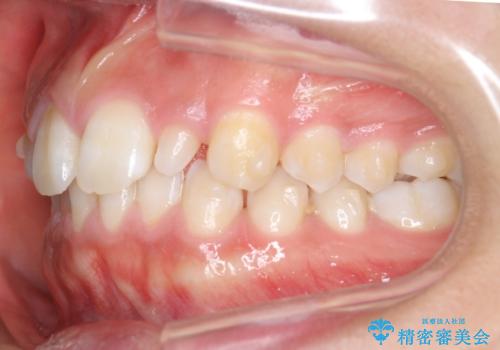

前歯のすきま 矯正治療とセラミックで小さな歯を形良く

- 前歯のすきまを気にして来院。

左上の2番が生まれつき小さく、スペースが余っていました。

右上の2番もやや小さめでしたが、相談の上、左上2番のみセラミックで形を整えることとしました。

そのほかの隙間はマウスピース矯正で閉じることにしました。

- 総額99万円 (矯正治療:85万円 左上2:ジルコニアクラウン スペシャル 13万円、仮歯 1万円)費用は治療当時の料金となります

当初はワイヤー矯正を希望されていましたが、右上7番の頬側に咬頭があり、ブラケットを貼ることが難しいため、こちらからマウスピース矯正をお勧めしました。